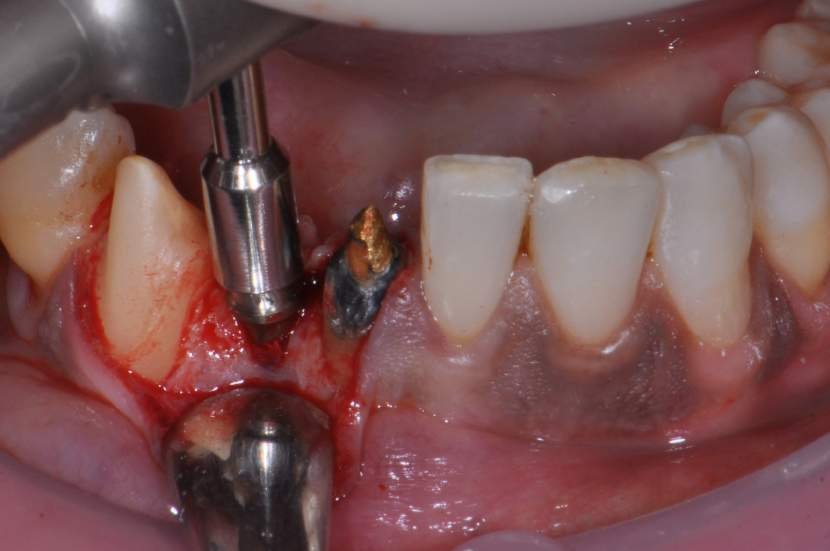

O procedimento cirúrgico para os implantes Slim segue um protocolo semelhante como outros implantes, porém muito simplificado. Normalmente utilizase a técnica anestésica infiltrativa. Um retalho mucoperiosteal deve ser rebatido para uma observação direta do rebordo ósseo disponível. No entanto, quando o tecido queratinizado e o volume ósseo abundantes estiverem presentes, uma cirurgia flapless é muitas vezes o protocolo cirúrgico de escolha.2

Para instalação de implantes de Ø 2.5mm é necessário apenas a utilização da fresa lança diâmetro de 2.0 mm. E para instalação de implantes de 3.0 mm utilização da fresa lança diâmetro de 2.0 mm e opcionalmente a fresa Countersink Slim 3.0mm (em casos de osso tipo I ou tipo II). O implante tem o ápice cortante e espiras que facilitam sua instalação. Os implantes Slim se apresentam de 1 em 1 mm de comprimento de 7 a 13 mm, o que facilita muito a escolha dos tamanhos no momento do planejamento.